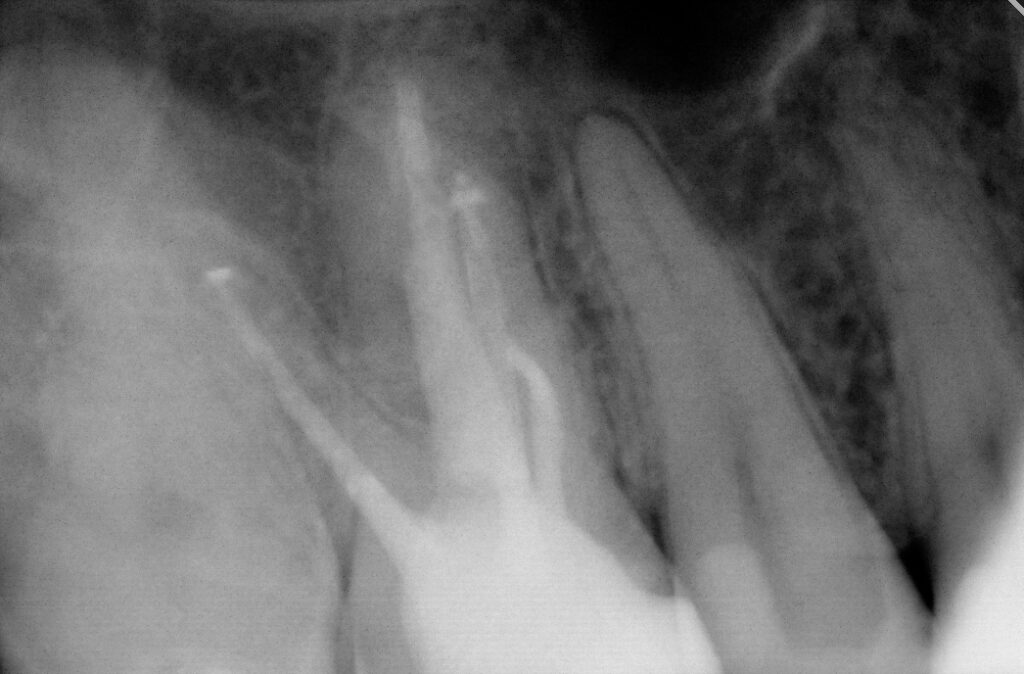

During the first visit, all carious tissues were removed, and the missing wall was restored using Asteria A3B material. The root canals were de-obturated, and a missed MB2 canal was identified. The canals were temporarily obturated with calcium hydroxide.